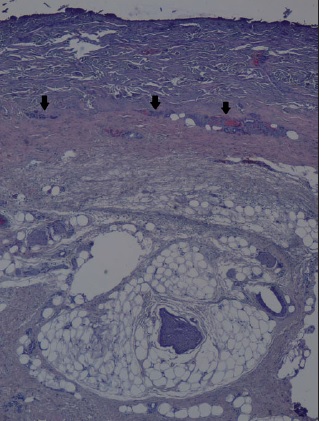

La realización de biopsias pre y postratamiento en 3 de los pacientes permitió observar 2 casos de desbridamiento parcial de la zona necrótica, siendo 1 caso una quemadura de tercer grado en dorso de mano que precisó de injerto (Fig. 25 a 34, caso 9), y el otro una quemadura previamente tratada con Flammazine Cerio® (Fig. 35 a 45, caso 12). En el tercero de los pacientes biopsiados apreciamos desbridamiento histológico completo de la zona necrótica con preservación de la dermis sana (Fig. 46 a 50, caso 11). Como hallazgos significativos, en las 3 muestras postratamiento evidenciamos un infiltrado inflamatorio linfocítico perivascular (Fig. 36, 40 y 48).

Otro hallazgo significativo de nuestro estudio es el incremento del infiltrado inflamatorio tras el tratamiento (Fig. 36, 40 y 48). Sin embargo, no podemos afirmar que sea consecuencia del tratamiento enzimático ya que no realizamos comparación con zonas de quemadura no sometidas a tratamiento con Nexobrid®. Además, en la literatura existe referencia al infiltrado neutrofílico típico que existe en la zona intermedia de la quemadura (región histológica comprendida entre la zona sana y la zona necrótica de la quemadura), pero el evidenciado en nuestro estudio es un infiltrado linfocítico perivascular que, hasta donde nosotros sabemos, no aparece mencionado en ningún estudio publicado sobre el desbridante Nexobrid®.(21) Aunque desconocemos si este infiltrado es originado o potenciado por el tratamiento con Nexobrid® o bien debido exclusivamente a la progresión de la quemadura, sería necesario estudiar si el posible incremento del infiltrado inflamatorio guarda correlación con la velocidad de curación o con el pronóstico a largo plazo, o bien es únicamente el resultado de la evolución fisiopatológica de la quemadura y no existen diferencias con el infiltrado evidenciado en las quemaduras no tratadas con Nexobrid®.

Estudio histopatológico en 3 pacientes: desbridamiento completo de la quemadura en 1 y parcial en 2, con abundante infiltrado inflamatorio linfocítico perivascular postratamiento. Los hallazgos histopatológicos se correlacionaron con la eficacia del desbridamiento valorado clínicamente en 1 de los 3 casos, y con el diagnóstico clínico de la quemadura en los 3 casos.